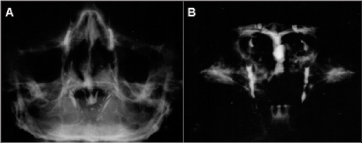

All patients who presented an abnormal Jones I test were submitted to dacryocystography and nasal endoscopy evaluation. The main alteration observed in the dacryocystographic examination was nasolacrimal duct dilation which was completely permeable to the contrast (Figure 1 A, B, C, D).

The nasolacrimal duct dilation was bilateral in 11 patients (22 nasolacrimal ducts) and unilateral in two (2 nasolacrimal ducts). Thus the dilated and permeable ducts were observed in 92.30% (24/26) of the lacrimal excretory systems evaluated by dacryocystography. The lacrimal sac was dilated in one patient (3.84% - 1/26) (Figure 2) and another (3.84% - 1/26) presented a nasolacrimal duct obstruction.

The dacryocystographic examination consisted of dilation of the inferior lacrimal punctum using a lacrimal punctum dilator and injection of an oily radiographic contrast material (Lipiodol - Guerbet) via a cannula into the inferior canaliculus of the lacrimal drainage system. The patient was then submitted to an X-Ray which allowed us to observe good opacification of the superior, inferior, common canalicui and nasolacrimal ducts at the medial aspect of the orbit in the anterior-posterior view. Contrast could normally be seen exteriorizing into the inferior meatus where the ducts empty(15).